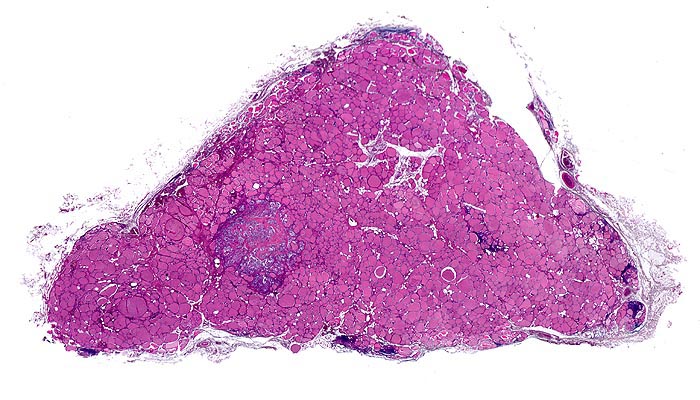

PathoPic – image database / PathoPic ID 4850 - medulläres Schilddrüsenkarzinom bei MEN 2A

medulläres Schilddrüsenkarzinom bei MEN 2A

maligner Tumor

Schilddrüse

Unauffälliges Schilddrüsenparenchym mit spärlichen Entzündungsinfiltraten und einem relativ scharf begrenzten Tumorknoten.

Mehrere scharf begrenzte weisse Knoten in beiden Schilddrüsenlappen von bis zu 8mm Durchmesser.

Beim Vater der Patientin wurde ein bilaterales Phäochromozytom diagnostiziert und in der Folge eine multiple endokrine Neoplasie vom Typ 2A. Im Familienscreening wurde bei der Patientin eine Mutation im Ret-Protoonkogen nachgewiesen und eine prophylaktische Thyreoidektomie durchgeführt.